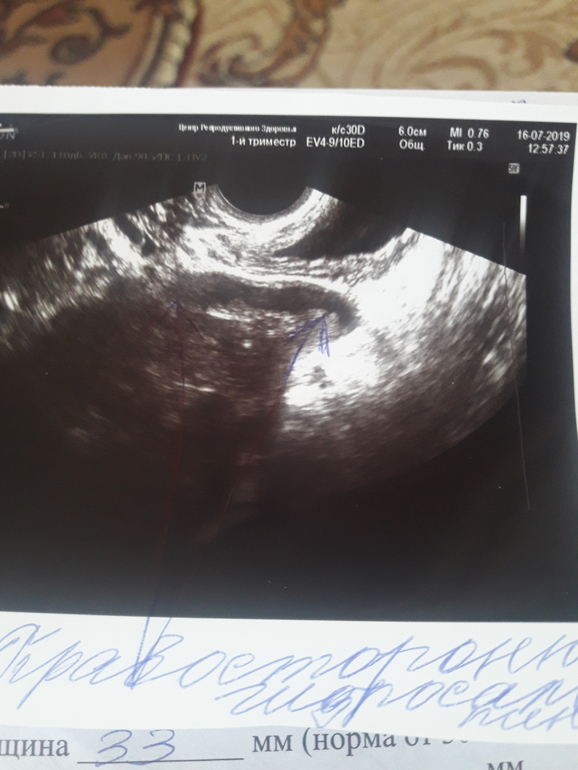

ОТЧЁТ : ну что ж, сделала я операцию, только не лапару а обычную( хирург так посчитала нужным) . До операции прошли стимуляцию и в крио ушли 6 отличников))). Ну и вот лежу в больнице и вспомнила свой пост и как сама искала ответы. На узи труб видно не было, и смотрели хорошие специалисты. Но хирург на ощуп сказала и по этому фото что я оставила после гсг что будем оперировать. Мы договорились, если можно оставить, то оставлят. Итог : трубы все в спайках, в обоих трубах жидкость - гидрос, расширенные всего до 1 см и выглядели как сосиски. Удалили без раздумий. Это была причина моей ЗБ !!!

Мне очень повезло с новой ре, с хирургом которая согласилась на операцию, потому что гидрос мне нигде не ставили!!!! Когда я об этом говорила мне крутили у виска, что я дура!!!!